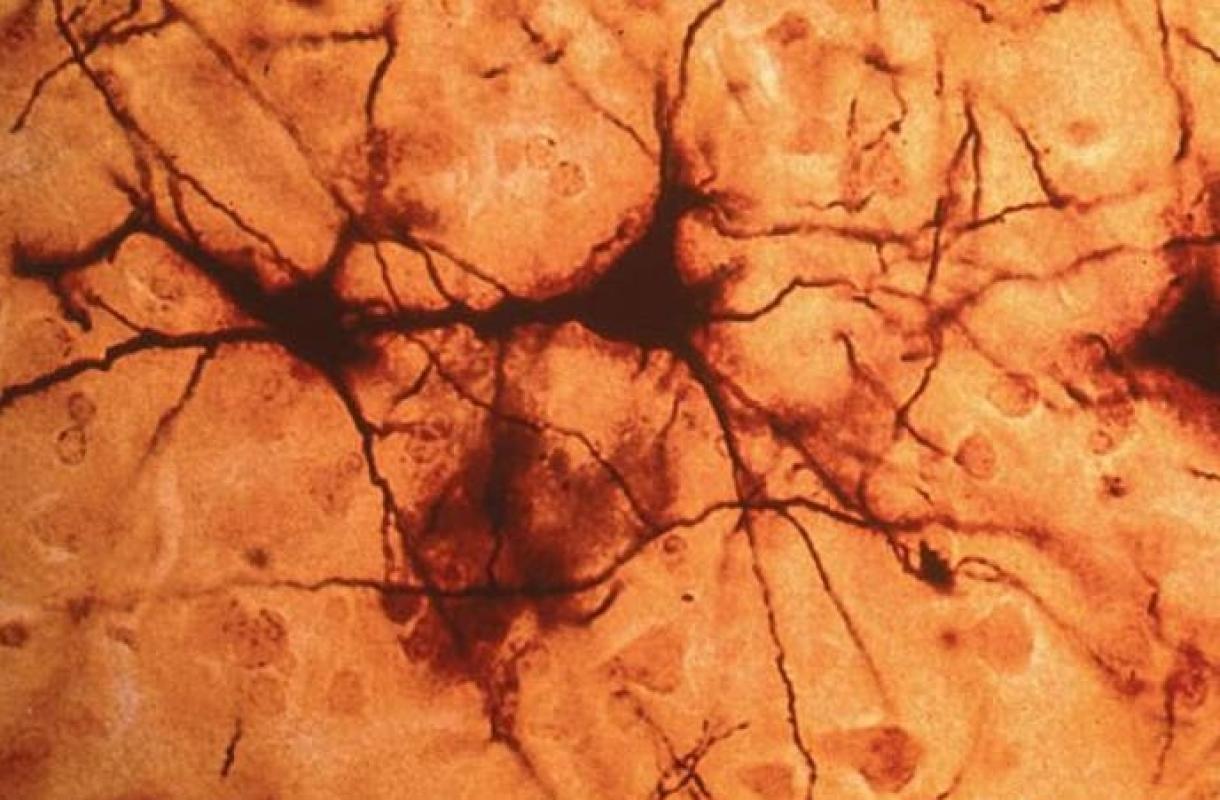

Un reciente estudio realizado por miembros de la Facultad de Medicina de Yale explica cómo interactúan las neuronas que están a punto de morir frente a las células llamadas gliales, las responsables en eliminar células muertas, y todo lo que esto puede significar para el cerebro.

En el artículo llaman a esta técnica “2Phatal”, donde, utilizando marcadores fluorescentes logran observar cómo las células gliales se comunican entre ellas haciendo posible detectar de esta manera a las células muertas.

Los investigadores descubrieron que los tres tipos de células gliales funcionan de manera coordinada y eliminan con solvencia las células muertas y cualquier otro desecho que detectan a su paso.